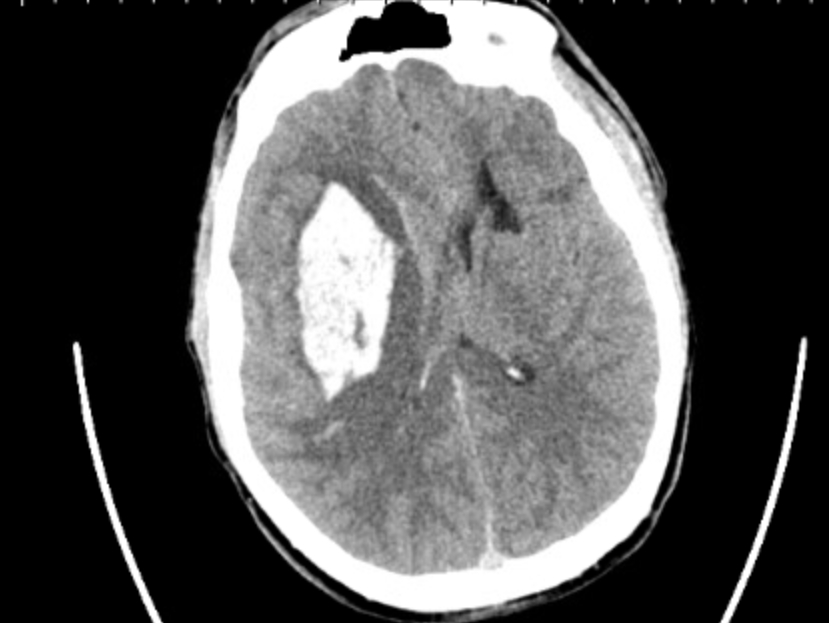

Case Summary: In less than 400 words, please summarize the case. Briefly describe the case and any particular complexities and/or complications encountered.: An 18-year-old male with past medical history of right basal ganglia (BG) intracranial hemorrhage (ICH) at age 6, hypertension, seizures, recurrent gastrointestinal (GI) bleeds, G-tube dependent, subdural hygroma requiring multiple pseudomeningocele taps, developed an episode of slurring of words, worsening left sided weakness, and unresponsiveness at the age of 17 years 6 months. CT head showed recurrent bleed in right BG and was taken for hemicraniectomy and evacuation. A subsequent MRI Brain revealed a left BG infarct.

DSA showed no AVM but presence of microaneurysm at left distal lenticulostriate artery and dissecting aneurysm at left calcarine artery. The patient was discharged to acute rehabilitation. MRA brain completed 3 months later showed multiple hemorrhagic foci in the brain parenchyma and old lacunar infarcts in the deep gray and white matter, concerning for a genetic etiology.